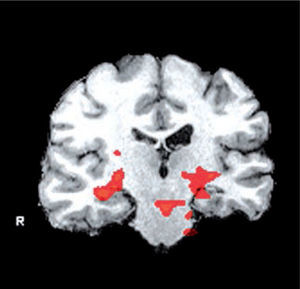

Por último, se han desarrollado técnicas de resonancia magnética funcional (fMRI) que corresponden a pruebas similares a los test clínicos pero realizados al interior del resonador que permiten una evaluación de las áreas funcionales, especialmente en relación a la memoria y funciones cognitivas muy útiles en los pacientes con alteraciones del sueño (Figura 6).